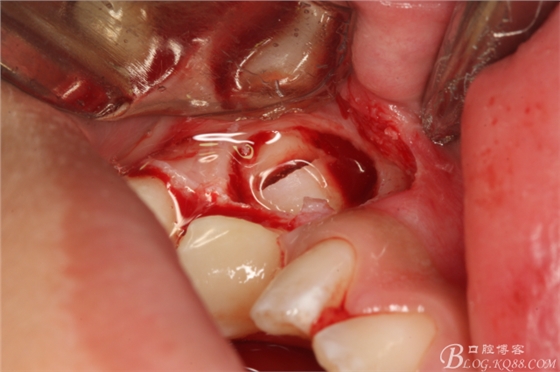

圖6.暴露35牙冠

圖7.橫斷牙冠與牙根